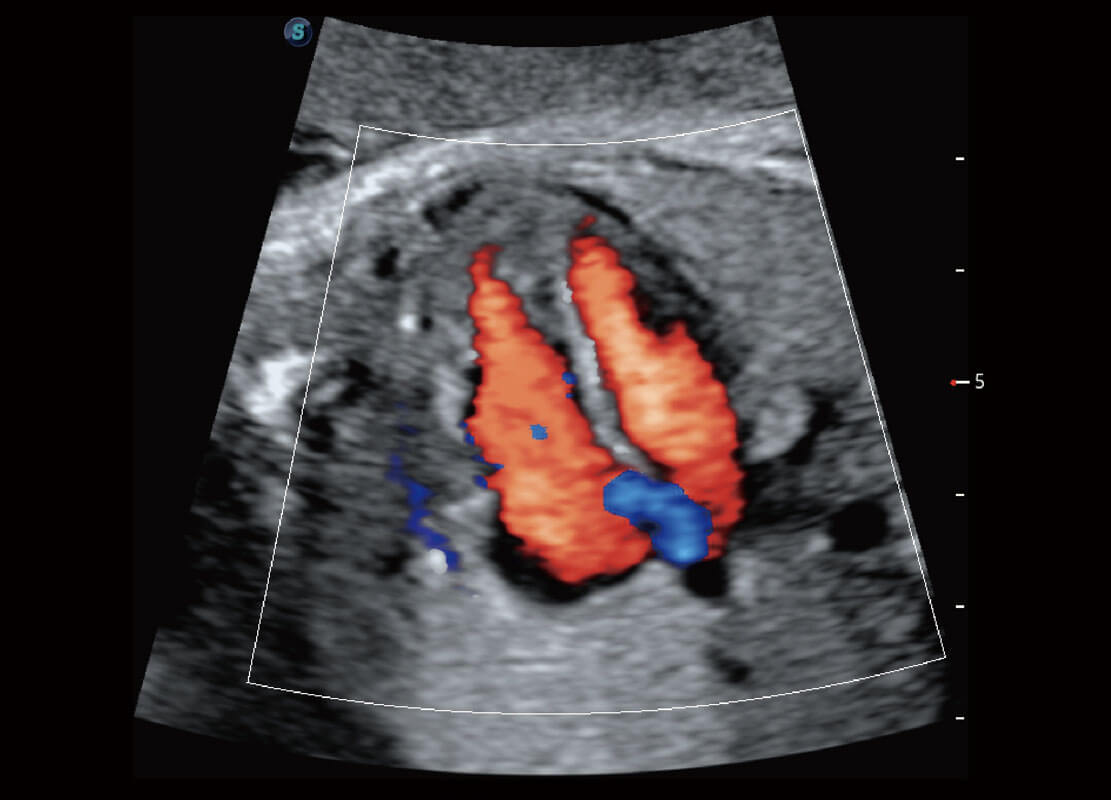

• 腔内妇科-宫腔分离

• 腔内妇科-卵巢